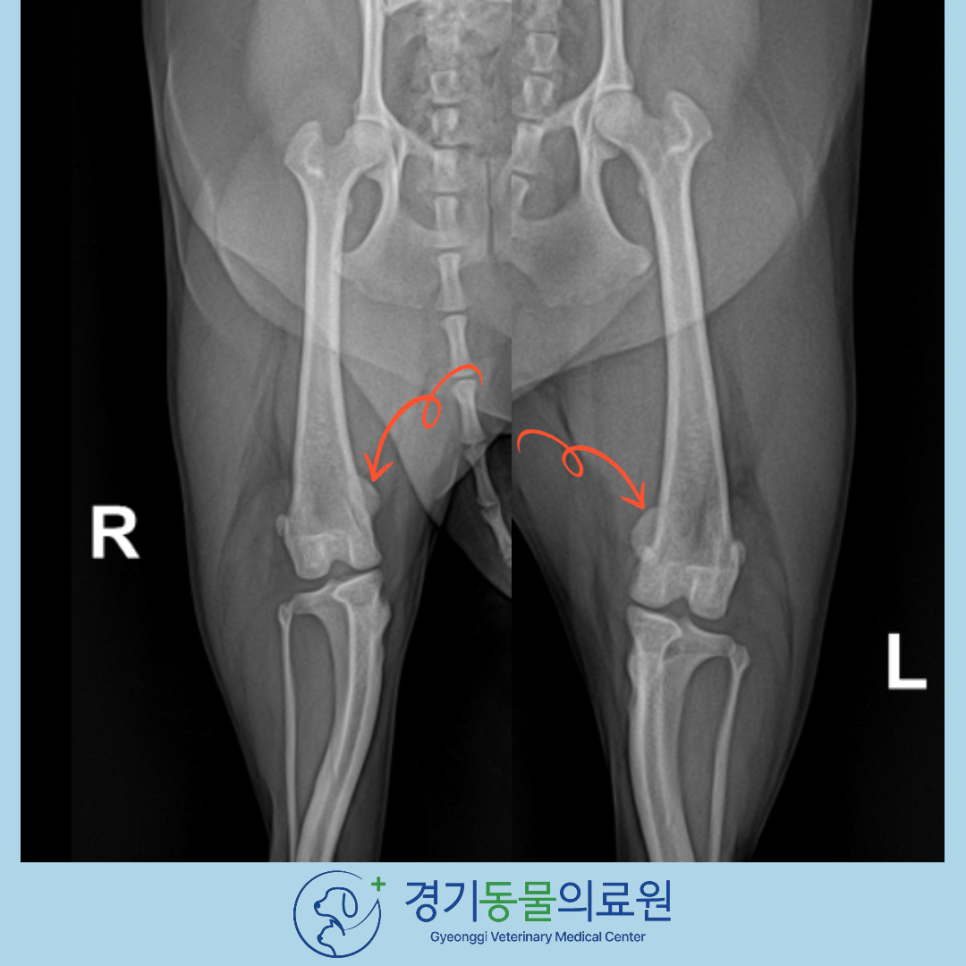

▶ 수술 전 방사선 검사

방사선 검사 상에서도 양측의 내측 슬개골탈구가 확인되었습니다.

슬개골 탈구는 크게 4단계로 나눌 수 있습니다.

보통 슬개골 탈구 수술을 위해 내원하는 환자들의 경우 3기 이상이 대부분이지만,

1기 혹은 2기라 하더라도 통증을 나타내거나 진행 속도고 빠른 경우에는 수술적 교정이 필요합니다.